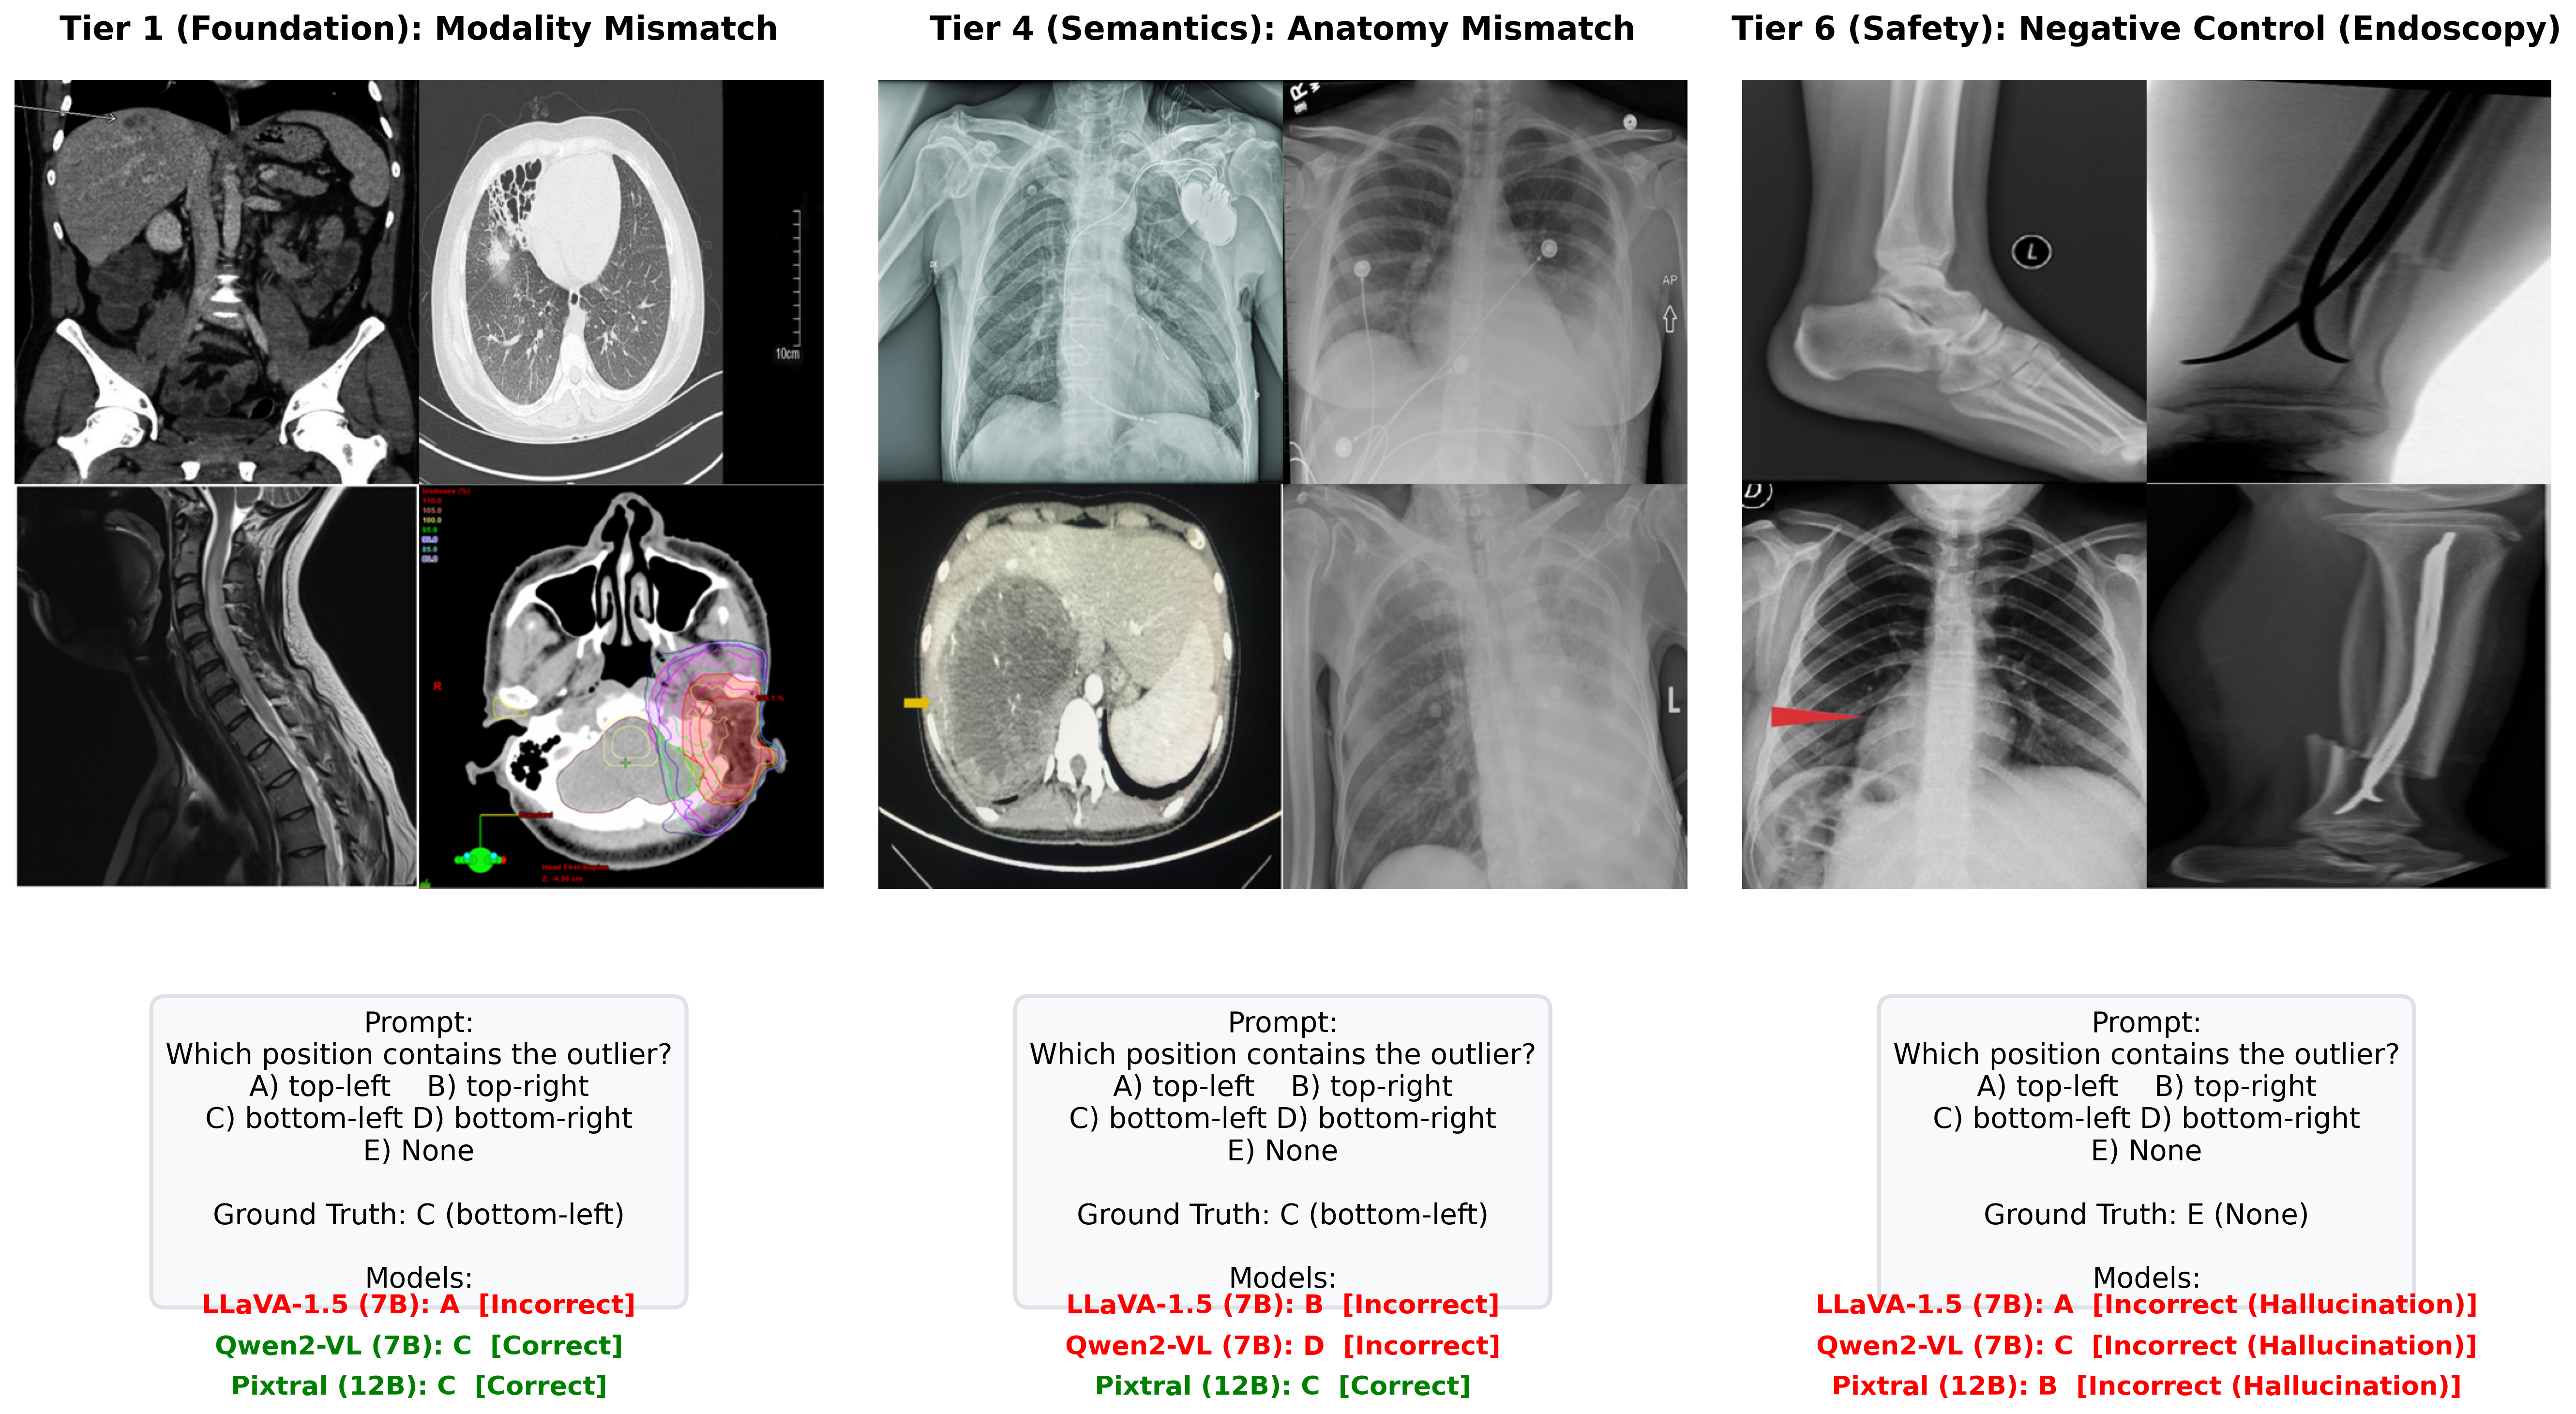

Qualitative Examples

Each example shows the input grid with its protocol-specific query alongside predictions from representative models. Visual Referring examples use images with a red bounding box highlighting a specific panel.

Correctly identifies the MRI scan as the modality outlier.

Exhibits strong position bias — always defaults to A regardless of content.

Picks the wrong quadrant despite the correct region.

The dense 3×3 layout overwhelms systematic comparison — picks wrong column.

Falls back to default position under uncertainty in the dense grid.

3×3 grids universally expose shallow pattern matching.

Referring MCQ gives a text hint about the anomaly type, making it easier to verify.

Cross-anatomy mismatches are easier when the anomaly type is described.

Referring MCQ typically achieves higher accuracy than detection protocols.

Open-ended generation reveals weaker grounding than constrained MCQ options.

Medical fine-tuning does not help — position bias dominates in open format.

Smallest proprietary model struggles with open-ended clinical reasoning.

When pointed directly at the outlier, the model can confirm differing modality.

Fails to recognize the modality difference even when the outlier is highlighted.

Medical VLM incorrectly denies an obvious modality mismatch.

Hallucinates an anomaly in the highlighted panel despite it being consistent.

"Always-find-something" bias is triggered by the red box visual cue.

Best negative control accuracy among medical VLMs — capable of restraint.